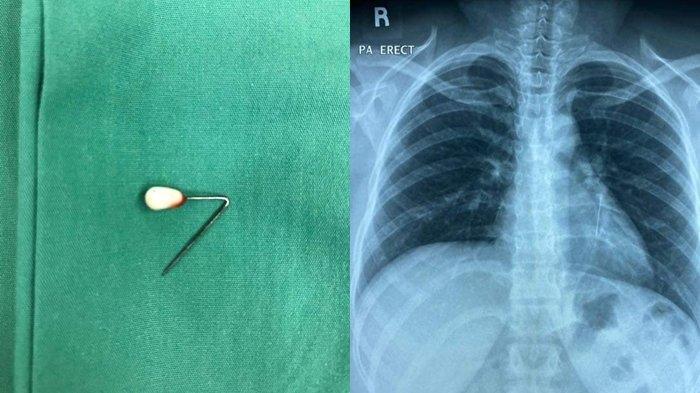

SRIPOKU.COM -- Beginilah nasib gadis yang tak sengaja telan jarum pentul saat hendak mengenakan hijab.

Awalnya, jarum pentul itu digigit saat mengenakan hijab. Kemudian wanita itu tersedak, dan jarum pun tertelan.